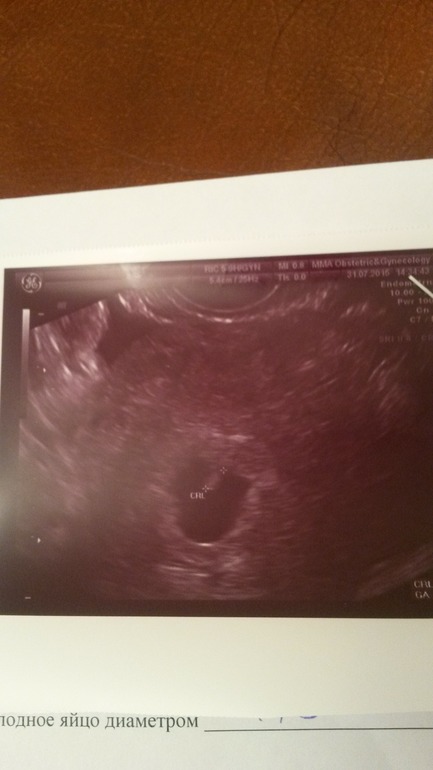

Узи на 28 дпп. Долгожданное сердцебиение )

Я БЕРЕМЕННА !31 июля все таки наступил и мы с мужем отправились на узи. Ожидание свелось к минутам. наконец услышала от врача "все хорошо! " и показал мне эмбриончика с едва заметным шевелением. Это, как сказал врач сердцебиение. 140 ударов /мин. Муж ожидал в коридоре и признался впоследствии, что его ритм сердца не уступал )). Надо же, а когда шли туда, он выглядел вполне даже спокойным. Вот пишу и слезы катятся )). Господи, дай нам сил и терпения!

Плодное яйцо, как мне показалось чем-то напоминает сердце 💖, дм 15 мм. Ктр эмбриона 4,4. Дм желточного мешка 4.5. Хорион по кольцевидной стенке. Тонус матки отсутствует. Такие дела. В общем, идем дальше!